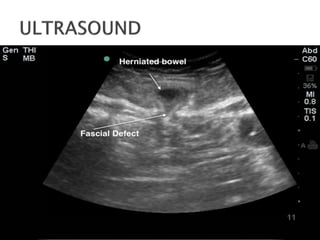

 History  Physicalexamination Physical examination of patients with hernia is usually remarkable for bulge in the groin, painless scrotal mass and palpable abdominal mass may be present. Abdomen  A palpable abdominal mass in the flank may be present  Abdominal distention Genitourinary  Painless scrotal mass may be present  Bulge in the groin